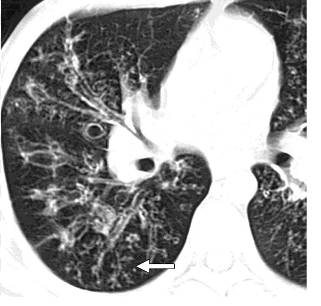

气道侵袭性曲霉菌病,右下肺外周部大小不等,结节影与分支线状影混合,分界不清

(4)非结核分歧杆菌感染(NTM):非典型NTM其CT和HRCT的病变好发部位和病变形态与肺结核类似;非典型NTM的CT和HRCT表现病变形态有小叶中央型结节及周围线样分支影即树芽征。

非结核分歧杆菌感染:高分辨率的CT扫描显示右肺多个结节分布于分支线状影周围,支气管扩张壁增厚,黏液嵌塞,支气管肺泡灌洗确诊。